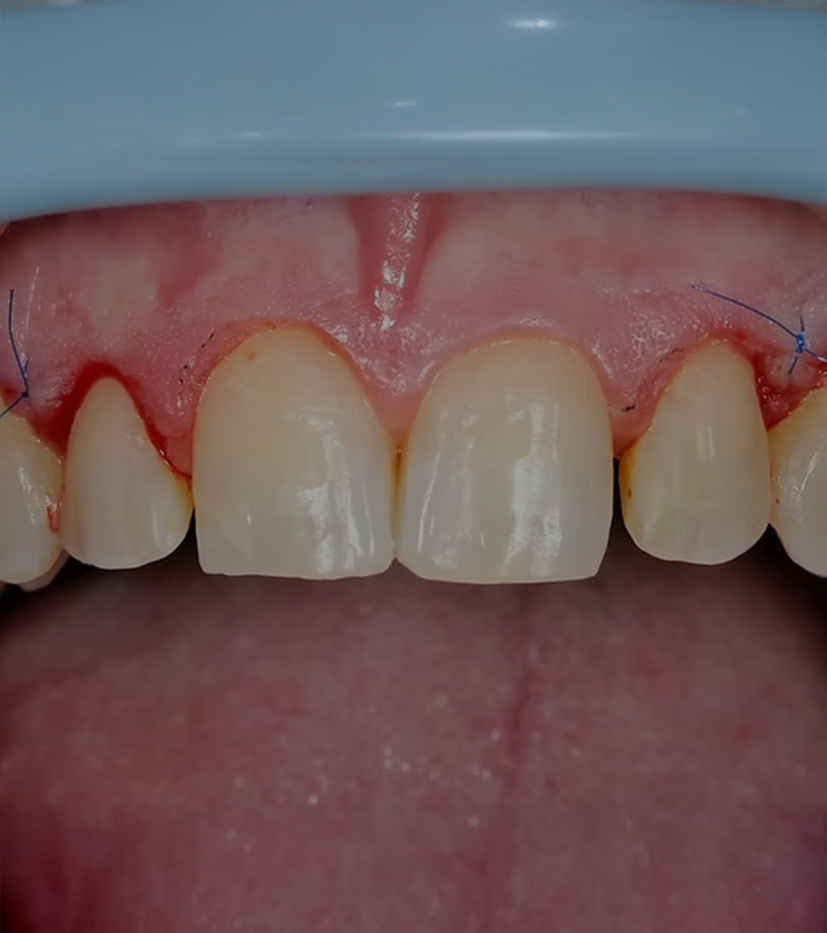

Temizleme ve dikiş atma:

İşlem tamamlandıktan sonra diş etleri iyice temizlenir ve iyileşmeyi desteklemek için dikişler atılabilir.

Takip:

Hastalar genellikle diş etlerinin düzgün bir şekilde iyileştiğinden emin olmak ve gerekirse dikişleri almak için diş hekimine veya periodontiste bir takip randevusu için geri dönecektir.